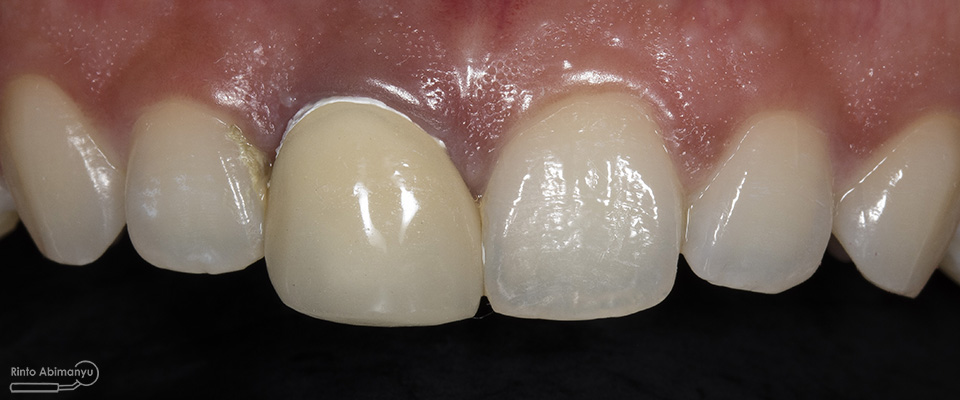

Begini kondisi klinis saat datang…

Foto klinis gigi-gigi anterior yang mengalami fraktur